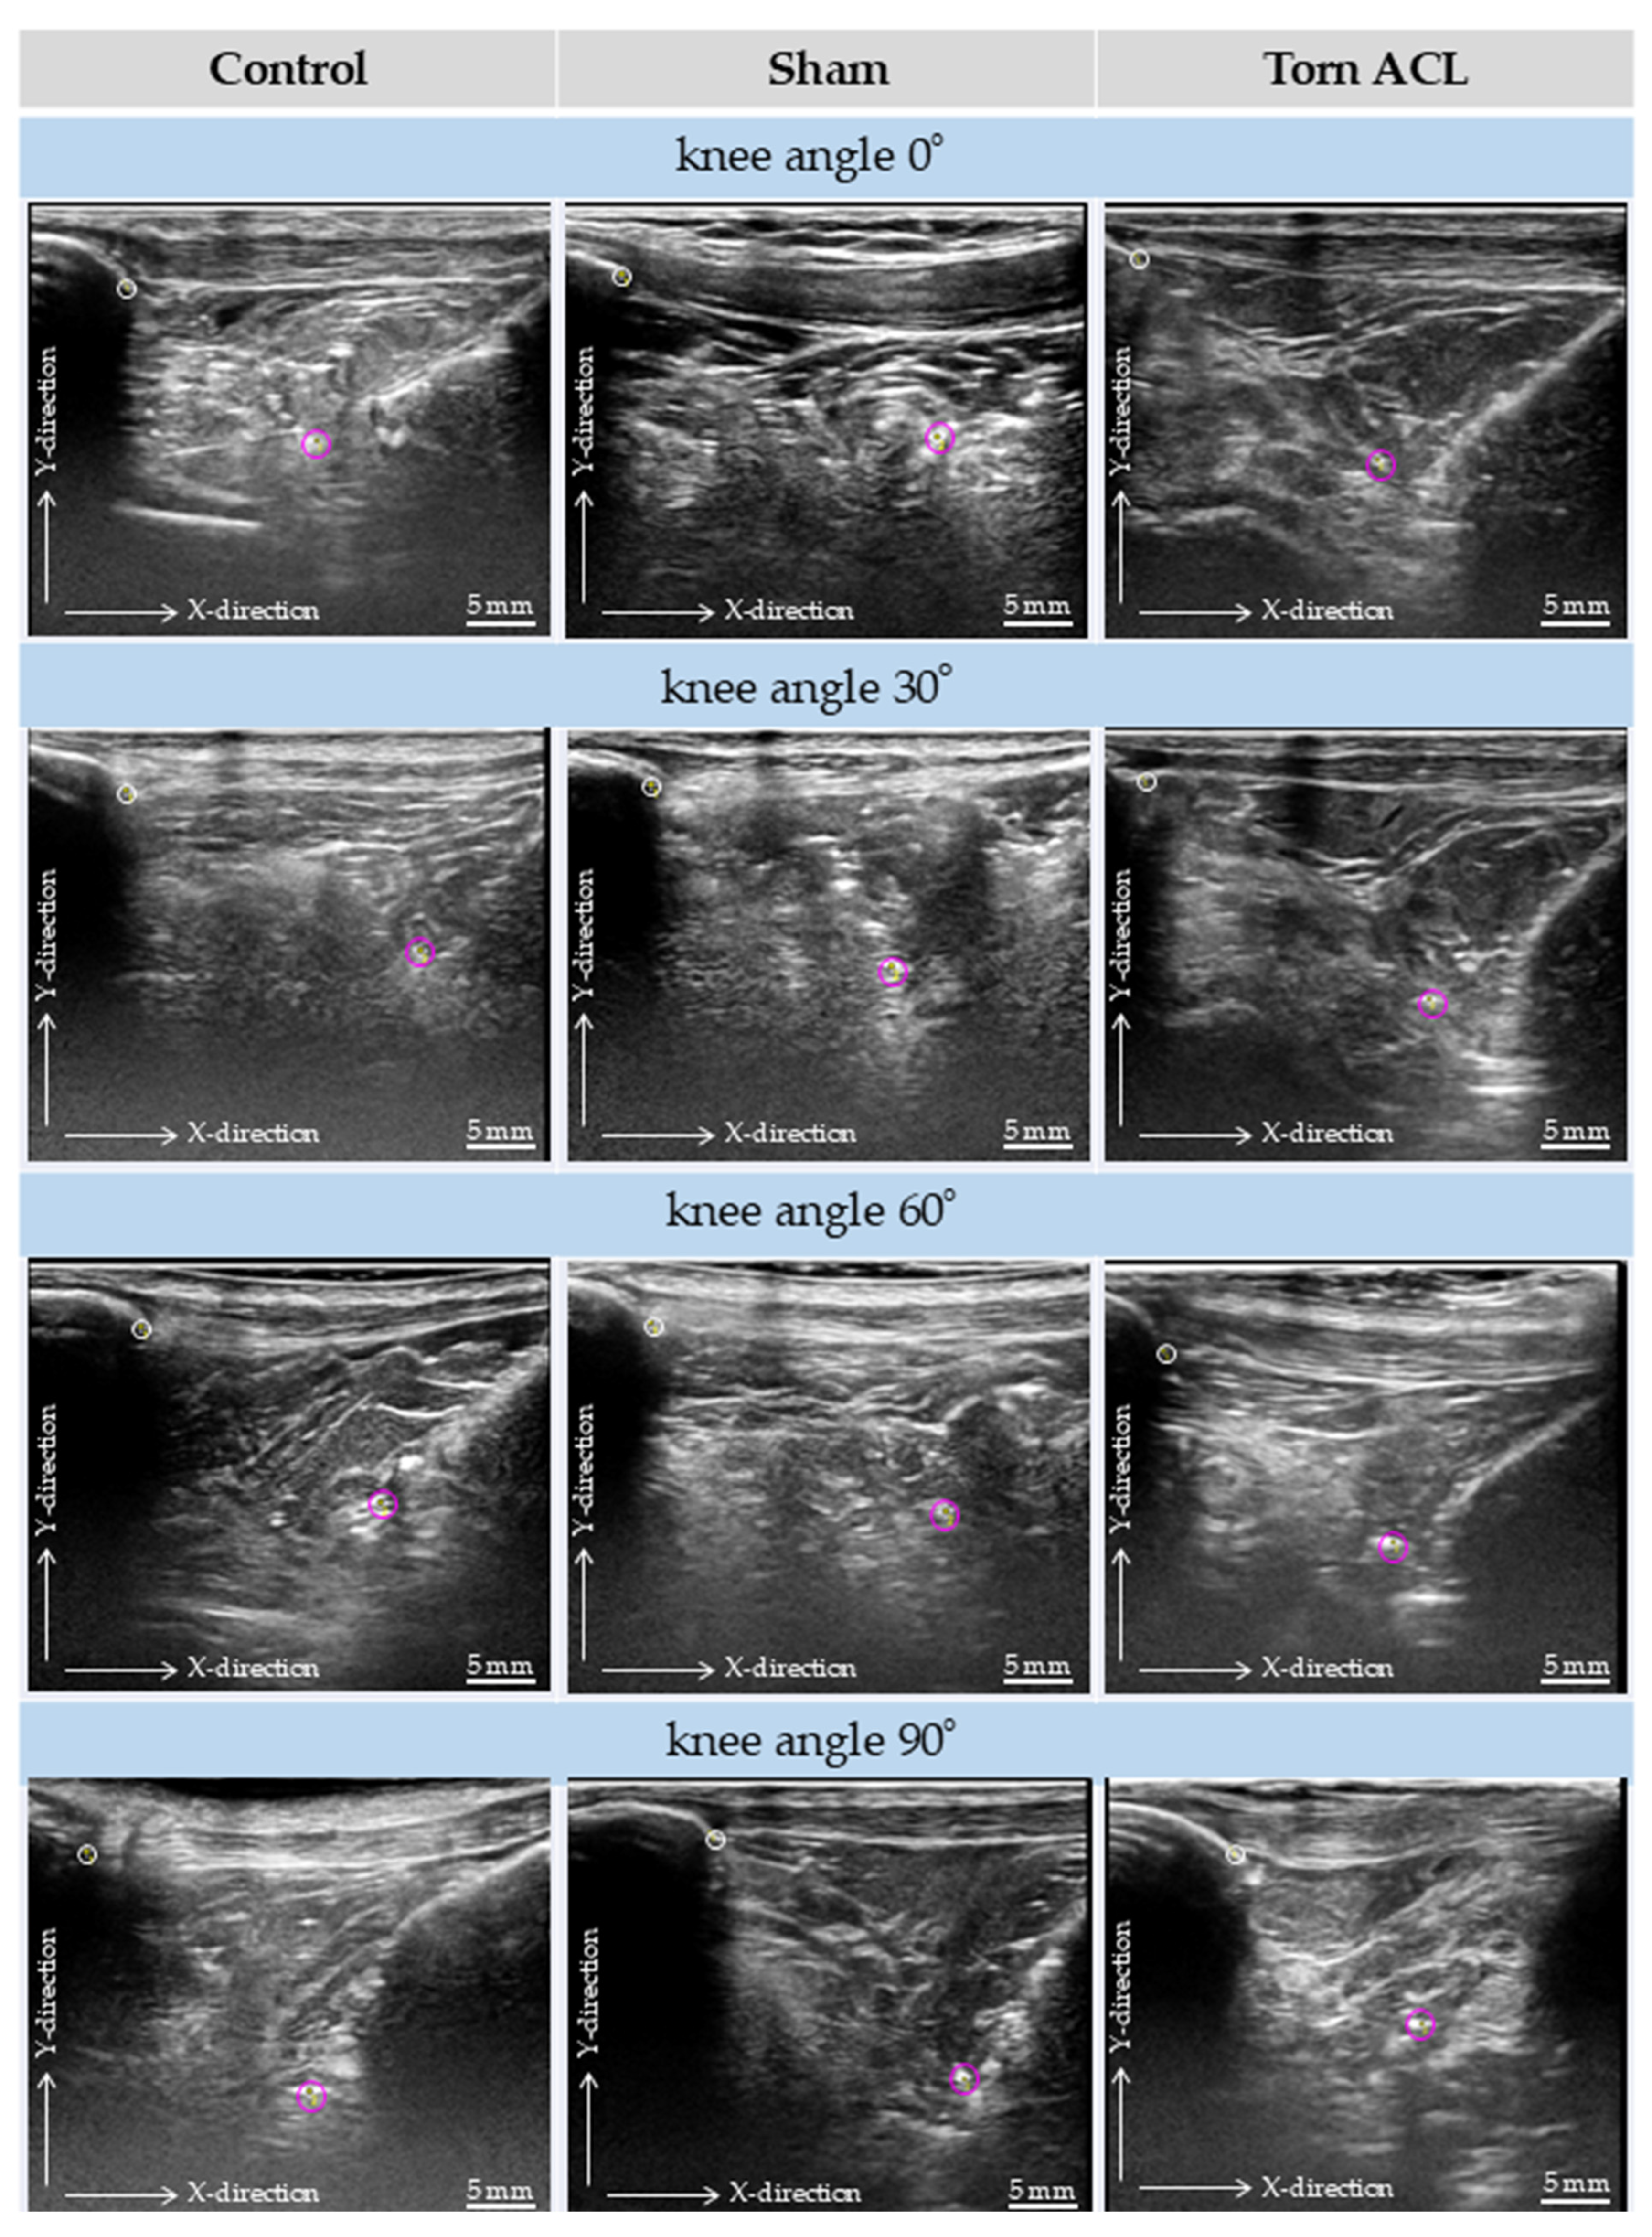

3.2. Qualitative Ultrasound Observations

3.3. Quantitative Kinematic Assessment and Reliability